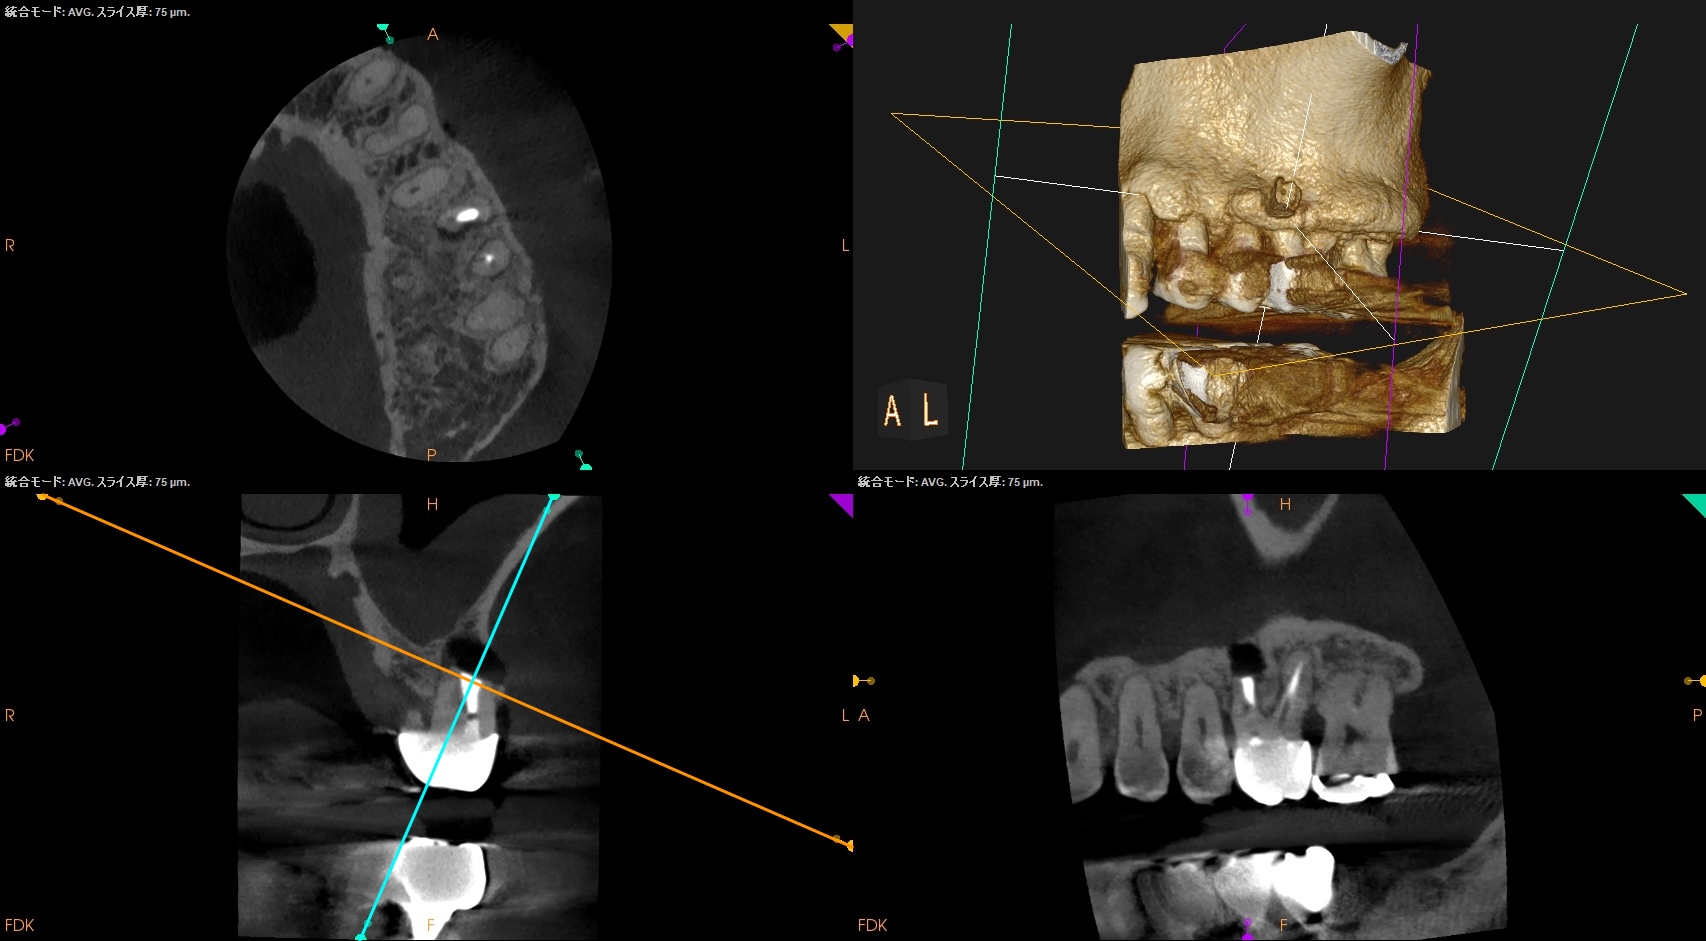

私の頭に思い浮かんだの以下のケースだ。

のように逆根管充填しても治癒するだろうが、

中心に対して左右非対称に近くなることから私は修正しない道を選択した。

つまり、

この状態でOKと判断したのである。

この治療の結果が出るのは半年〜1年後であるのでまたこの日の記事の続報はご報告したい。